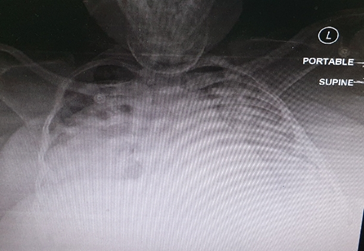

An interview was held with the relatives of the patient to discuss alternative treatment solutions to enhance oxygenation and reduce the inflammation of the lungs.11 The family members were asked to select either of these two treatment solutions: the provision of venovenous extracorporeal membrane oxygenation (ECMO) support or the trial of an off-label use of high dose of unfractionated heparin (UFH) through nebulization. At the end of the interview, the patient’s family appended their signature in an informed consent form to commence the administration of a high dose of UFH through nebulization. A dose of 25,000 units/mL was administered to the patient at 6 hours interval. On the second day, the physicians noticed a marvelous improvement in the P/F ratio after the administration of nebulized UFH. The P/F ratio of the patient increased from 80 to 280 mmHg on the second day to 390 mm/Hg on the seventh day. The physicians also noticed that there was a remarkable reduction in the bilateral lung infiltrates and inflammatory markers, which was evident in the patient’s chest radiograph (Figure 2).

Figure 2 Chest x-ray on Day 3 after starting heroine nebulization showing marked improvement.